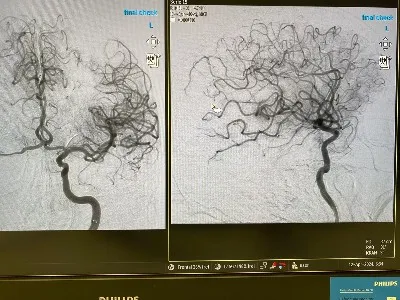

Intrygujący przypadek miał miejsce niedawno w SRH Waldklinikum Gera, kierowanym przez dr. med. Kroeßnera. Przypadek ten dotyczył użycia cewnika aspiracyjnego Glutton (6F) wraz z urządzeniem do pobierania stentu Dredger (4X40).

Zabieg skupiał się na trombektomii wewnątrzczaszkowej w obszarze tętnicy środkowej mózgu, z wykorzystaniem technik aspiracji i pobierania stentu. Podkreśla to znaczenie zaawansowanej technologii i wspólnych wysiłków w opiece zdrowotnej.